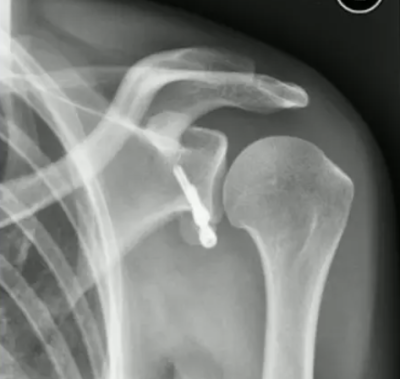

X-ray of Latarjet procedure

In both Latarjet procedure and Bristow procedure, it will cut the edge of coracoid process and resituate it to the glenoid edge with using screws, once a hole/tunnel is made.

These procedures sometimes cause complications.